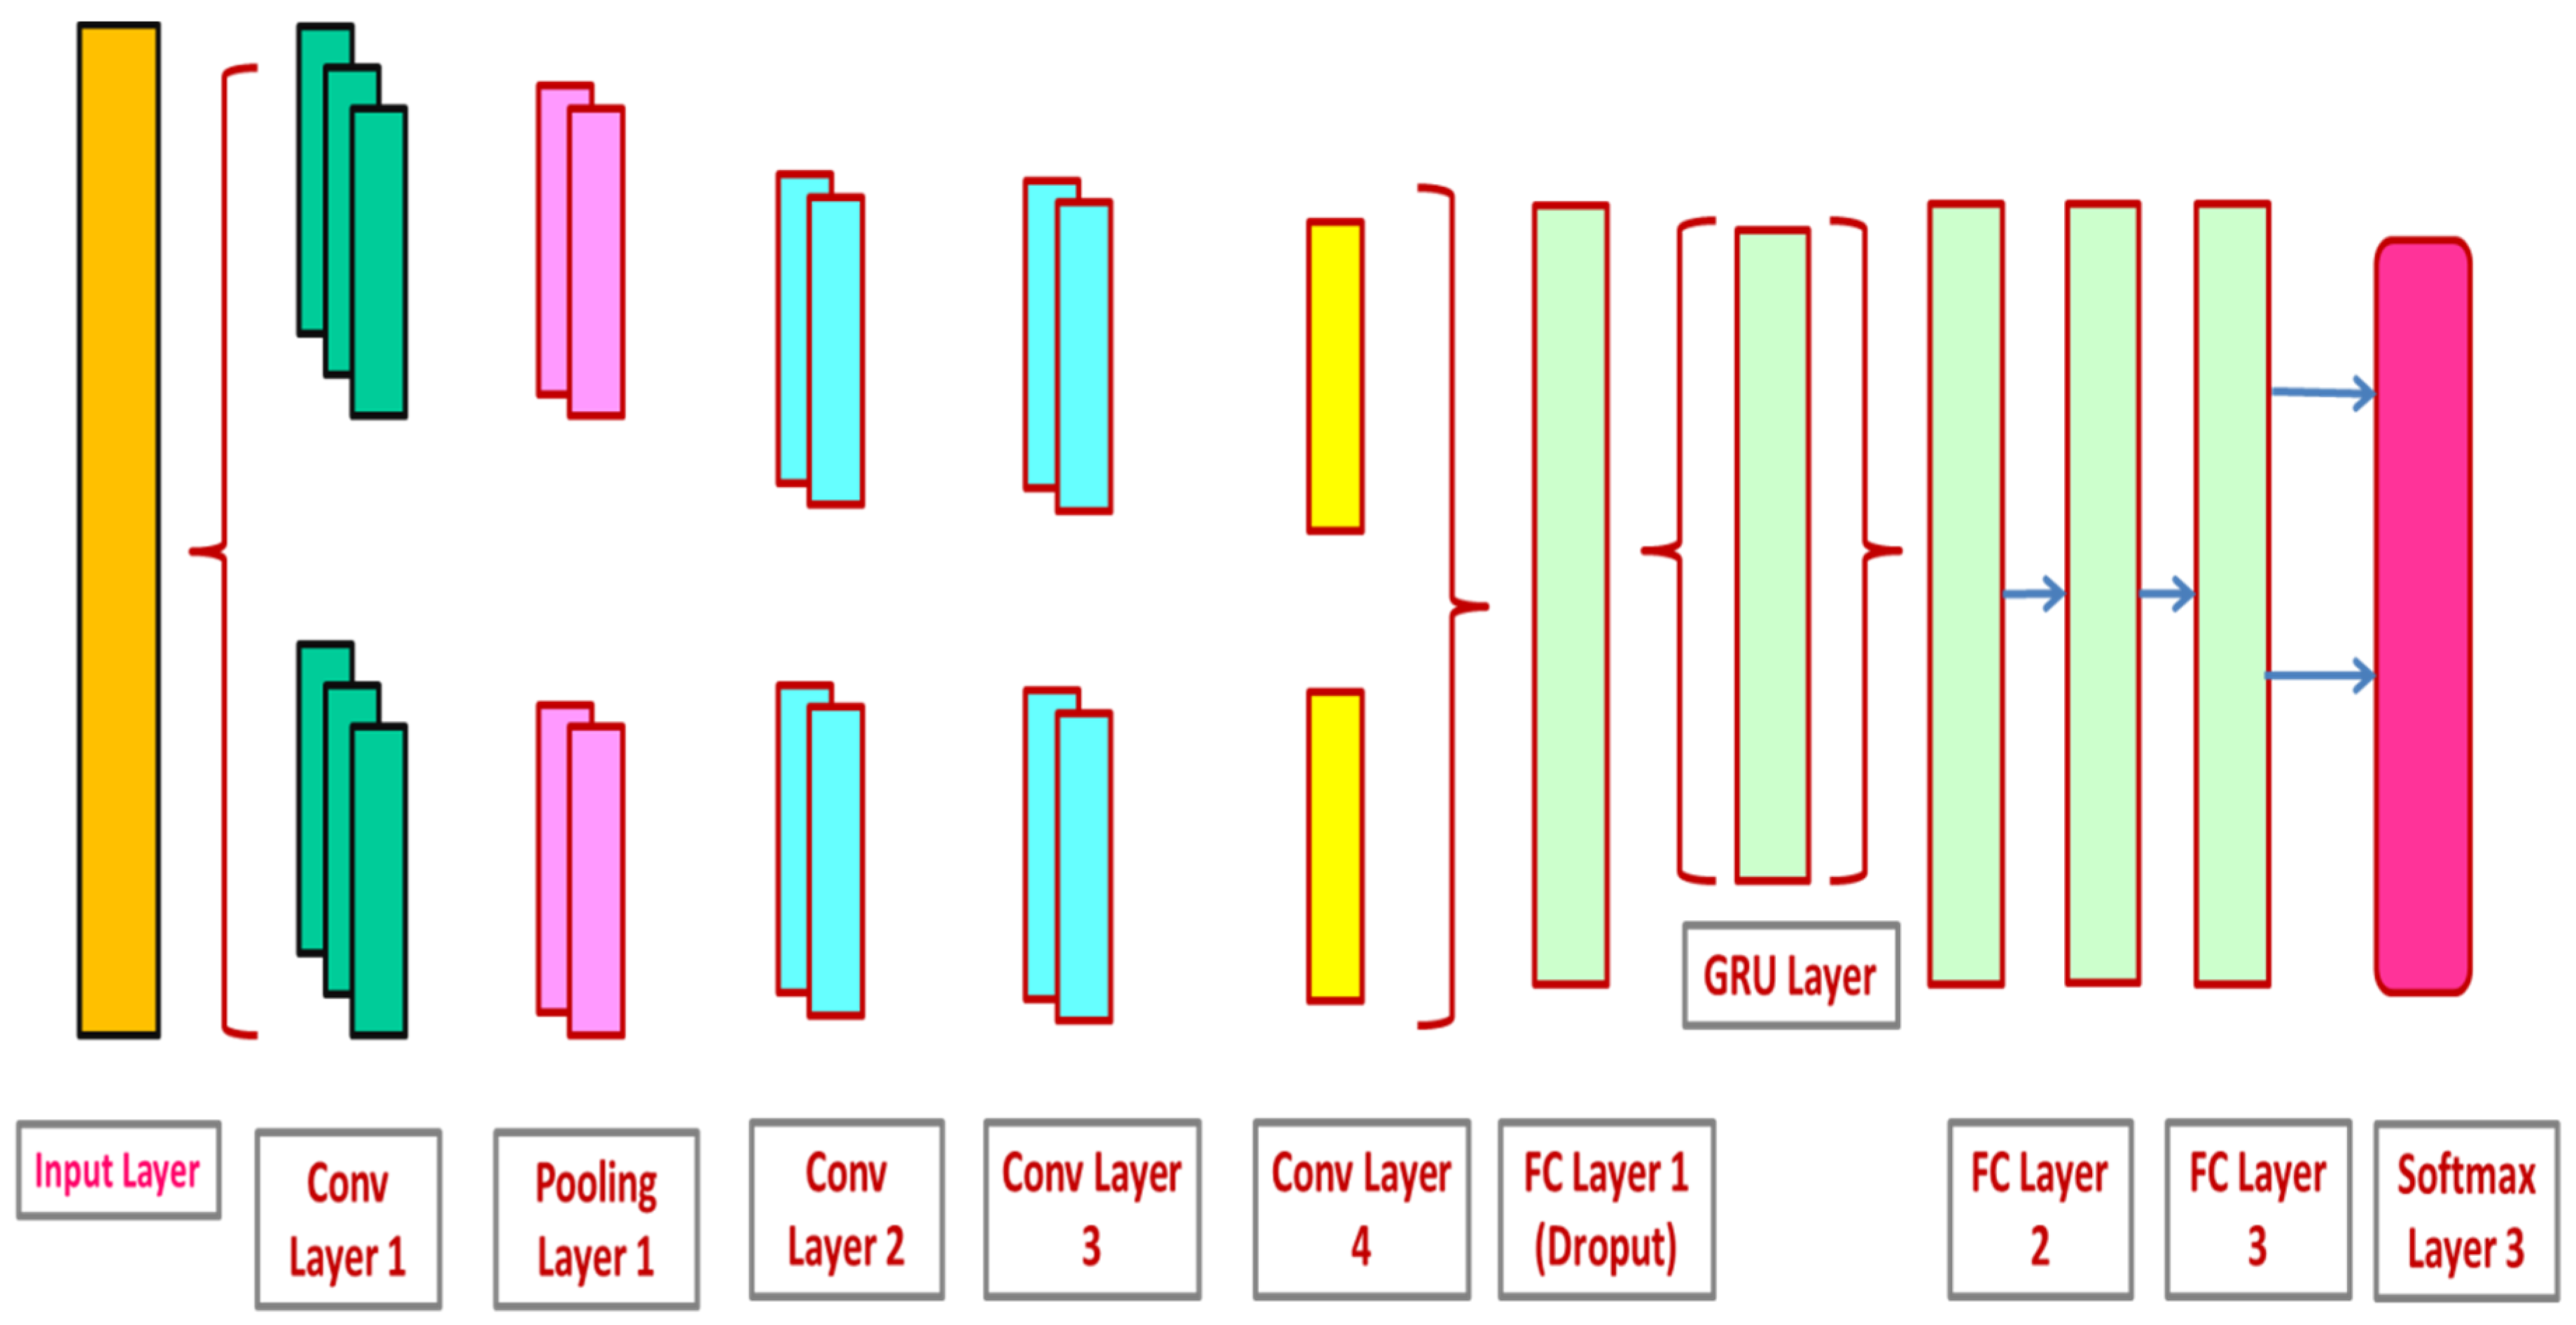

3.3. CNN and GRU-Based Lung Nodule Classification

3.3.1. Convolutional Neural Networks (CNN)

3.3.2. Gated Recurrent Unit Network (GRU)

3.3.3. CNN-GRU